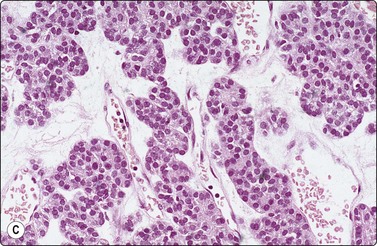

image image image

Fig. 6.28 Poorly differentiated carcinoma

(A,B) Smears showing syncytial clusters of crowded small cells with hyperchromatic nuclei (A, MGG, HP; B, Pap, HP); (C) Tissue section, same case. (H&E, IP).

Poorly differentiated thyroid carcinoma

Diagnostic criteria

Hypercellular smears,

Single cells, solid, trabecular and insular pattern,

Marked cellular crowding and high nuclear : cytoplasmic ratio.

Until recently, thyroid carcinoma with a poorly differentiated insular pattern was considered to be a distinct entity, a thyroglobulin-producing neoplasm, intermediate in aggressiveness between well-differentiated and anaplastic thyroid carcinoma. Reports have appeared documenting cytological features in insular carcinomas such as high cellularity, dispersed and loosely aggregated cells, solid, cohesive trabecular or papillaroid structures, intact insulae, fragile, ill-defined, granular cytoplasm, oval, hyperchromatic nuclei, occasional INCIs and/or grooves.151-155 However, as insular pattern is often admixed with trabecular and solid growth patterns, the more suitable term ‘primordial carcinoma’ was suggested for this entity.156

The current concept of pure poorly differentiated thyroid carcinoma, as per the Turin proposal156 is one that shows a histologically mixed solid/trabecular/insular architecture, absence of conventional nuclear features of PC and the presence of one of the following three features: cells with convoluted (raisin-like) nuclei, a mitotic index of ≥3 mitoses/10 high-power fields and tumor necrosis. Most tumors are immunohistochemically positive for thyroglobulin and thyroid transcription factor 1, and a subset is also positive for p53.157 Ras mutations are common.

Smears in poorly differentiated thyroid carcinomas are hypercellular with single cells as well as cells in solid, trabecular and insular patterns. There is marked crowding of cells and tumor cells show high nuclear cytoplasmic ratios (Fig. 6.28).158